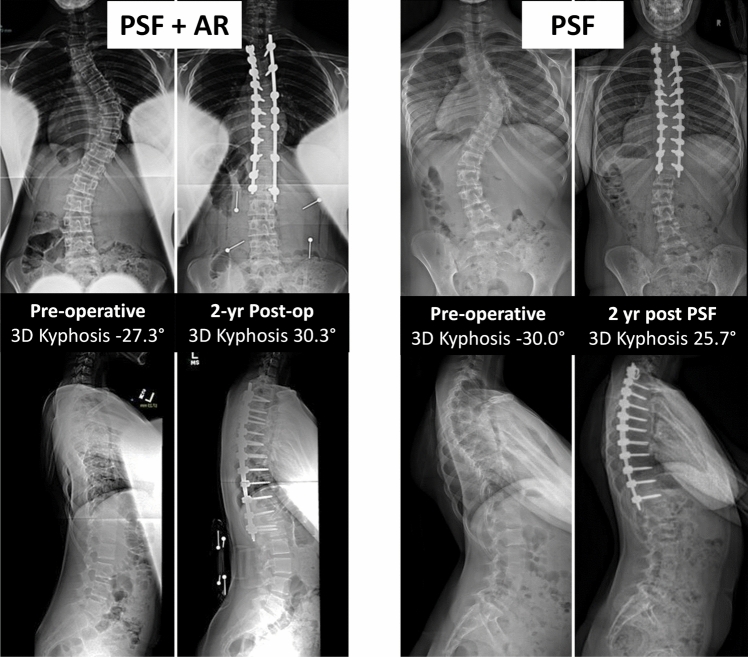

Results: 1384 patients were included with 53 (3.8%) undergoing PSF + AR. Mean preop 3D kyphosis was similar between PSF and PSF + AR groups (- 3.7° vs. - 0.5°; p = 0.08). PSF-AR had similar 2-year 3D kyphosis (23.0° [95% CI 20.5-25.4°] vs. 23.3° [22.9-23.6°]) and correction (26.7° [23.3-29.9°] vs. 23.7° [23.3-24.2°]) compared to PSF. When controlling for covariates, the models demonstrated no difference between approach (p = 0.058) or interaction of approach and preop 3D kyphosis (p = 0.31). Post-hoc power analysis showed an adequate sample size to detect a difference of 5° between approaches. PSF + AR had longer surgical times (324 vs. 266 min, p < 0.001) though no significant increase in overall complications (17% vs. 12.4%) compared to PSF alone.

Conclusion: In AIS patients with coronal curve < 70° and 3D hypokyphosis of 10 to - 40°, treatment with PSF + AR did not improve 2-year sagittal correction more than PSF alone. Surgeon identity and surgery recency influenced post-operative kyphosis more than any other patient or surgical factor.